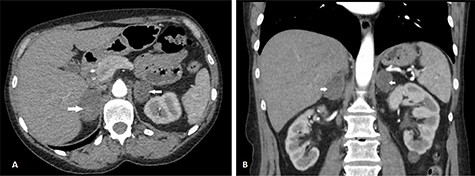

She had a non-contrast computed tomography (CT) of the abdomen to rule out urolithiasis. This showed features of right-sided pyelonephritis and small bilateral renal calculi but no ureteric calculi or hydronephrosis. BAH was confirmed on her triple phase renal CT scan (Fig. 1). She was started on intravenous fluids and broad-spectrum antibiotics (IV temocillin and gentamicin) to cover for suspected pyelonephritis. Her warfarin was held initially, and she was given vitamin K. Following advice from the hematologists, she was subsequently started on treatment dose of enoxaparin, but her platelet count started to decline, and this was changed to fondaparinux. On her second day on admission, she developed adrenal insufficiency evidenced by persistent hypotension, hyponatraemia of 122 mmol/L (reference range 133–146 mmol/L) and hypocortisolaemia of 40 nmol/L (reference range 100–500 nmol/L). She received intravenous hydrocortisone which was converted to oral steroids after 24 h. Her sodium level normalized by Day 8 of admission. Following 3 days of intravenous antibiotics, she was changed to oral amoxicillin, which was continued for 7 more days.

CT scan showing axial (A) and coronal (B) views of BAH (arrows). The right adrenal hemorrhage measured 35 × 52 mm axially and the left adrenal hemorrhage measured 40 × 33 mm.